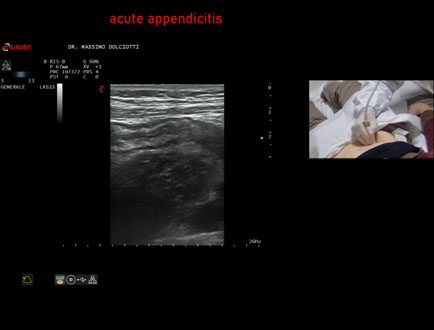

Data inserimento: 13/11/2025

Ecografia del: 10/11/2025

Strumento: Esaote MyLab Eight

Sonda: Lineare Multifrequenza 4-15 MHz

Età Paziente: M 26 anni

Motivazione dell'esame: da 2 settimane dolori addominali.

Commento all'esame: le immagini ed il video documentano il verme appendicolare, dello spessore trasversale di 9,1 mm e diametro longitudinale di 8,8 mm, con scarsi segnali di vascolarizzazione, da ricondurre ad appendicite in fase iniziale.

Conclusioni: appendicite in fase iniziale (early appendicitis).

Presentazione: Dr. Massimo Dolciotti - Ancona

Elaborazione digitale: Andrea Dini - Ancona